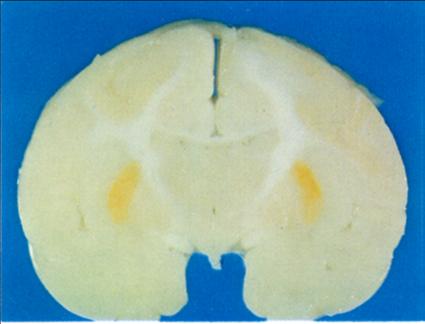

As can be seen in figure 4, Bilirubin staining is not

uniform in the brain, but affects the same subcortical

nuclei that are vulnerable to asphyxia at birth.

[20, p153].  Kernicterus is a developmental disorder

thought to be caused by high bilirubin levels in the

neonatal period.  However, in the experiments with

monkeys, Lucey et al. determined that bilirubin

staining in the brain only occurred in monkeys

subjected to asphyxia [19].

Figure 4: Non-uniform staining by bilirubin

(from Lucey et al. 1964)